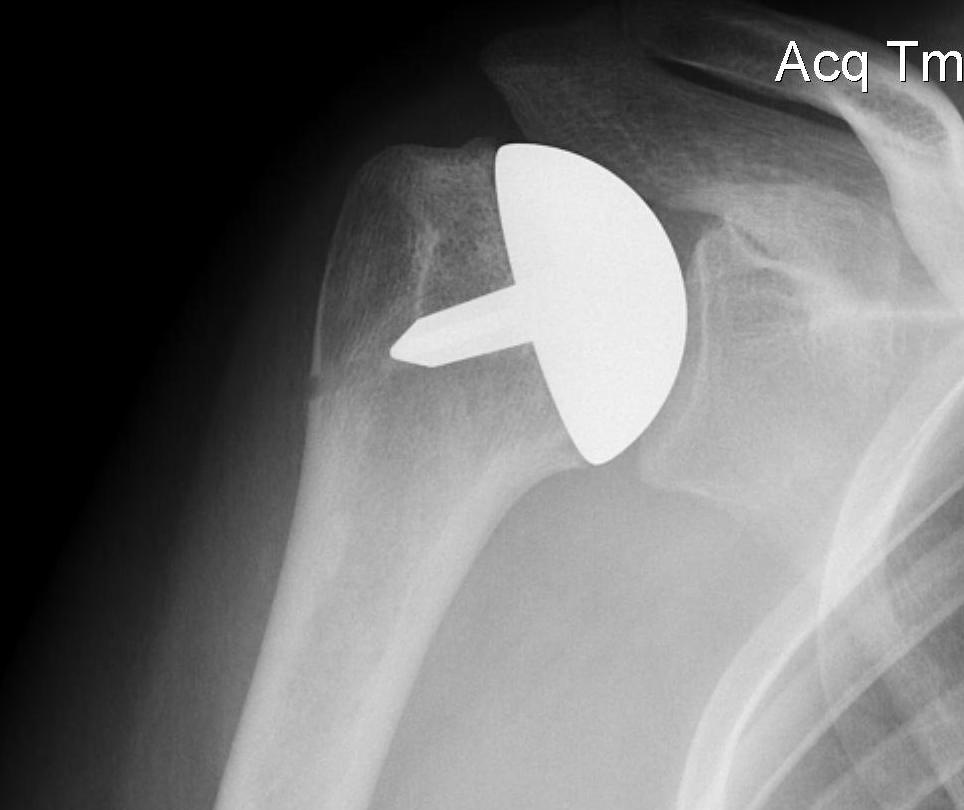

Fewer complications than TSR

Simpler procedure

OA